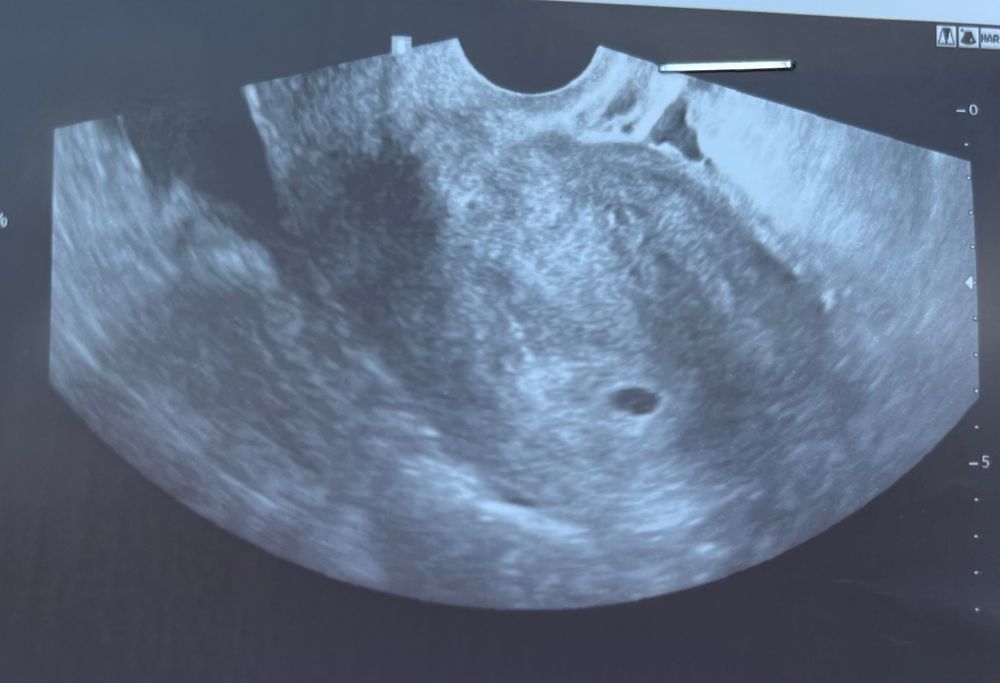

УЗИ на 20 дпп

Отличный размер ПЯ, намеки на ЖМ есть.

ПЯ отличный для вашего хгч! У меня на 17 дпп было 5300, на узи была на 21 дпп и ПЯ было 12 мм, и был жм. На 21 дпп уже у вас был бы жм 100%